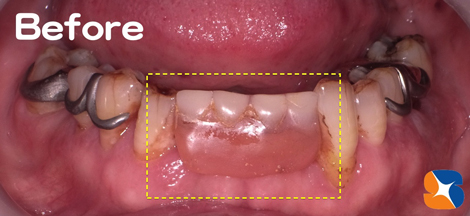

70代の紹介女性。主訴は「前歯がグラグラ。上の奥歯がない。噛む所がない。顔もくしゃってる」でした。

当院の入れ歯は、軽く、薄く、小さく、デザインにもこだわった渾身の入れ歯を保険料金で提供しています。最終、この様な入れ歯を装着することを目標に治療を始めた。 続きを読む